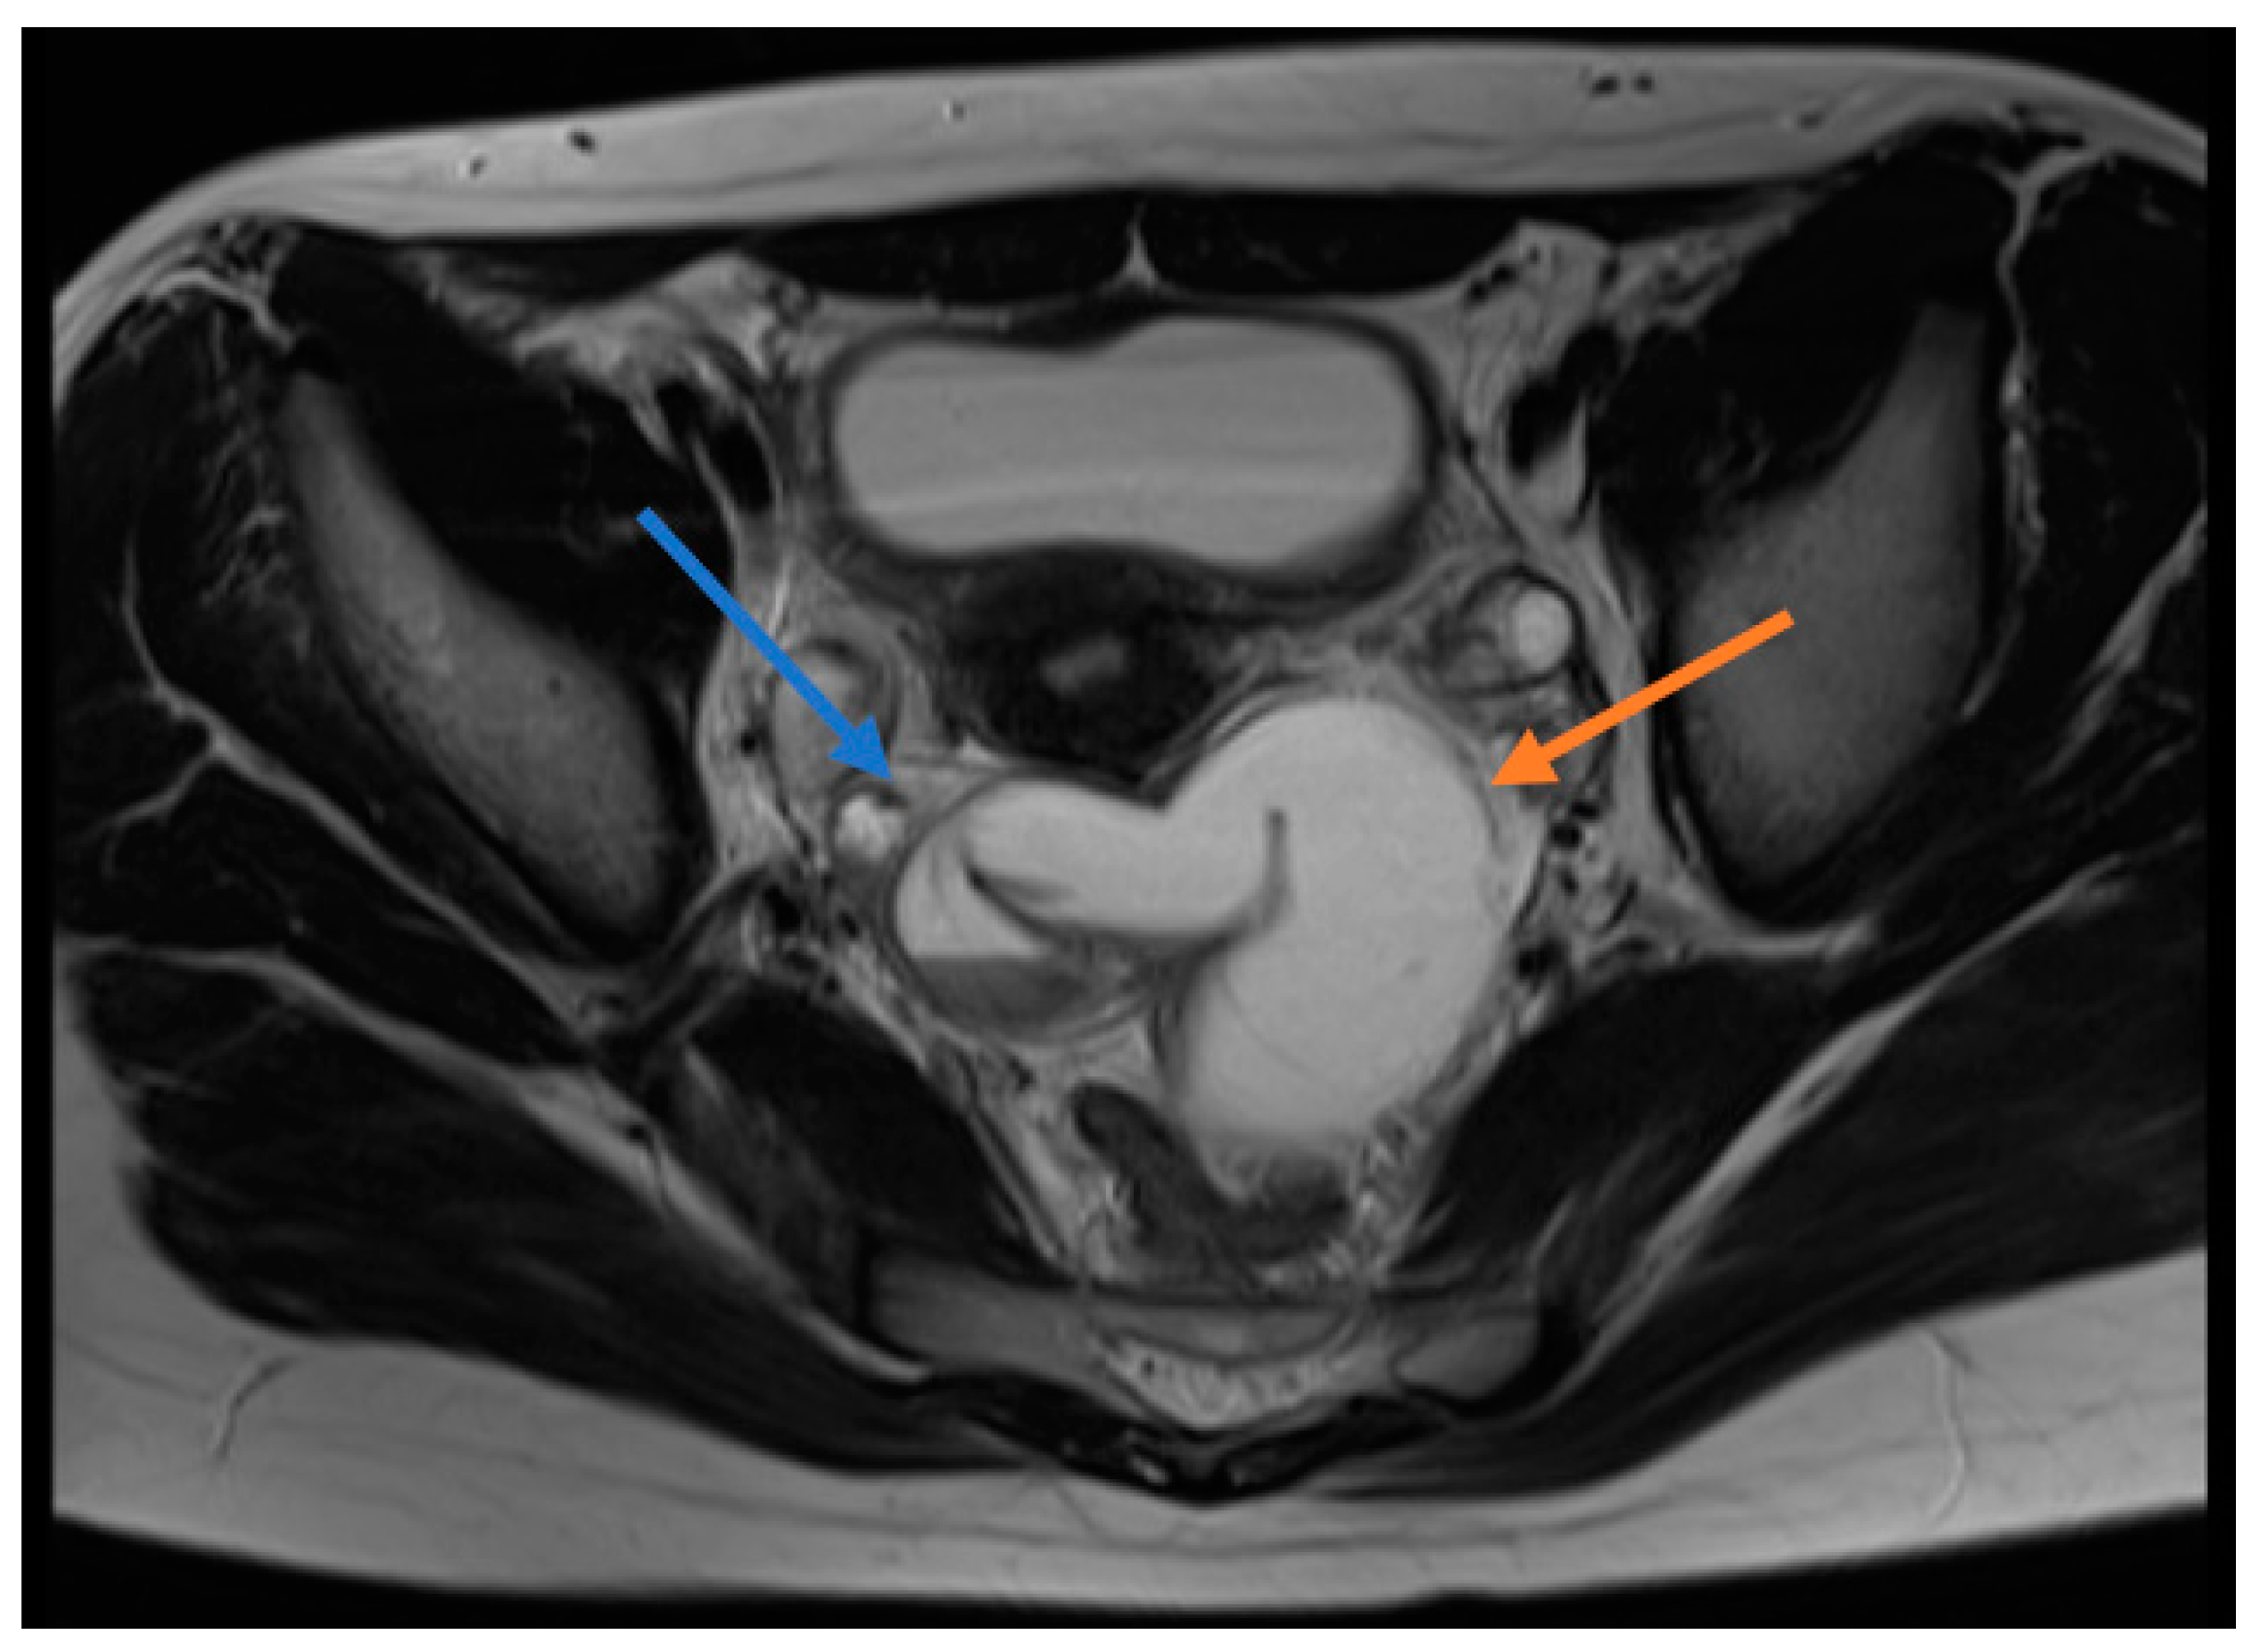

All patients underwent direct abdominal X-ray and Doppler ultrasonography (USG) and two patients underwent magnetic resonance imaging (MRI). The direct abdominal X-rays of all patients were evaluated to be normal. A paraovarian cyst/mass was detected in seven patients who had undergone ultrasonography, while two patients were evaluated to be normal. Because of the presence of free fluid in the pelvic region of one patient, it was considered to be an ovarian cyst. Four patients received the pre-diagnosis of ovarian torsion due to the absence or reduction of ovarian blood supply. Pelvic free fluid was identified in four patients and a paraovarian cyst was detected in five patients. MRI was performed on one appendectomized patient with the diagnosis of a paraovarian mass and this patient was preoperatively diagnosed with IFTT (Figure 1).

Figure 1.

Magnetic resonance image (MRI) of a patient diagnosed with preoperative isolated fallopian tube torsion. T1A sections show blue arrow torsion, red arrow indicates hydrohematosalpinx.

It is difficult to diagnose isolated fallopian tube torsion preoperatively since there is no pathognomonic imaging method, specific symptom or characteristic laboratory finding [14]. The diagnosis is usually made during surgical intervention. In our series, one patient was preoperatively diagnosed, while other patients were diagnosed during surgery. The MRI of the patient diagnosed preoperatively revealed thickened fallopian tube walls, tubal rotation and hydro/hematosalpinx, which were evaluated in favor of IFTT. Since there are no specific findings by US, the rate of diagnosis of fallopian tube torsion is low [15]. Cases are usually diagnosed with ovarian torsion, adnexal cyst or acute appendicitis. The preoperative diagnosis of four patients was ovarian torsion. Five patients were diagnosed with a paraovarian cyst on USG. IFTT was intraoperatively identified on the side where these cysts were present and torsioned fallopian tubes were removed when evaluated to be necrotic. Paratubal cysts, called hydatid cysts of Morgagni, are very rarely neoplastic [16]. In the study, the cystic structures that five patients had were diagnosed as a simple serosal cyst as a result of pathological examination. In our patient preoperatively diagnosed with a solid mass, only a cystic structure was found during the operation.